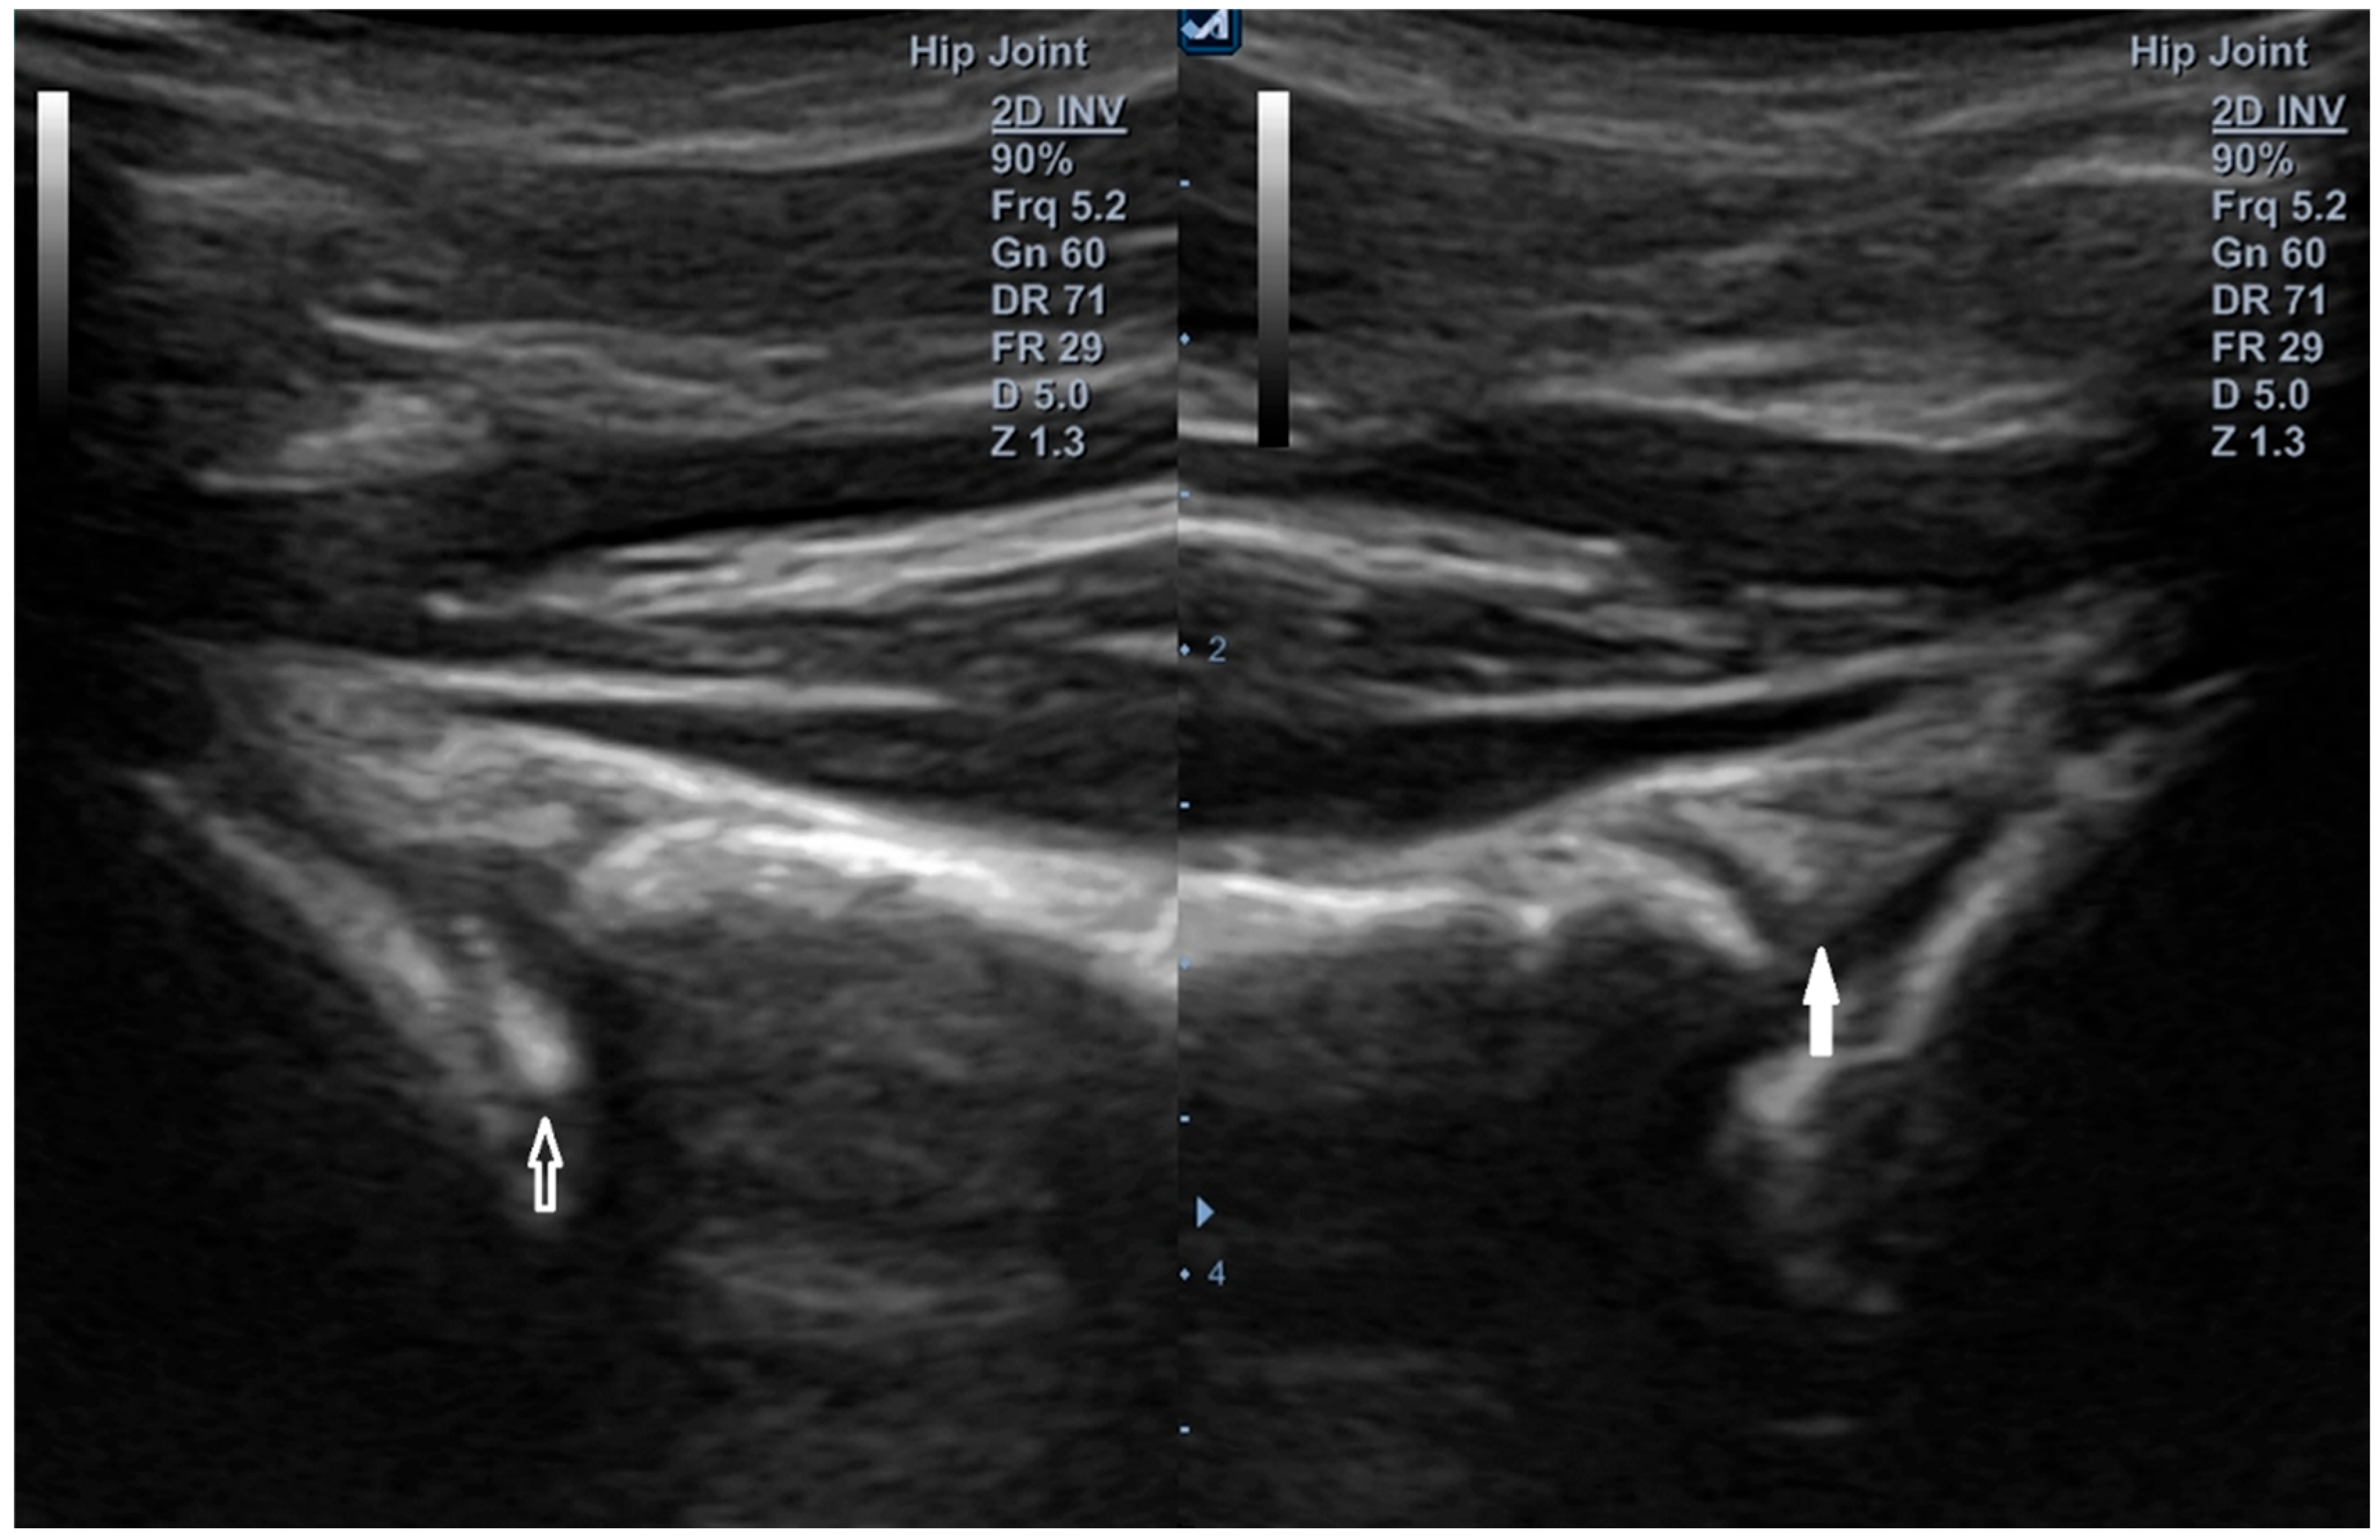

Figure 13. Anterior labral injury—assessment at the 3 o’clock position (Figure 3). Linear transducer with trapezoidal imaging (5–12 MHz). (Left): internal rotation of approximately 20°—the labrum is deformed and displaced medially. (Right): maximal external rotation—the labrum is reduced to its proper position under tension from the glenohumeral ligaments. Arrow, labrum.